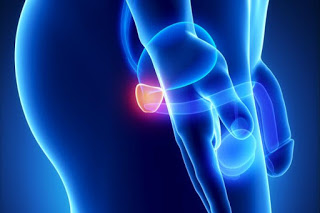

Δεκάδες χιλιάδες άνδρες , σε παγκόσμιο επίπεδο, σκοτώνει κάθε χρόνο ο καρκίνος του προστάτη, καθώς είναι ο δεύτερος σε συχνότητα καρκίνος, μετά τον καρκίνο του πνεύμονα!

«Δυστυχώς παρά την εξέλιξη των διαγνωστικών μεθόδων και μέσων χιλιάδες άνδρες πεθαίνουν κάθε χρόνο από καρκίνο του προστάτη, ο οποίος αν διαγνωστεί έγκαιρα είναι ιάσιμος» αναφέρει ο διαπρεπής χειρουργός ουρολόγος κ Βασίλης Πρωτογέρου Επικ. Καθηγητής της Ιατρικής Σχολής του πανεπιστημίου Αθηνών, με αφορμή την ουρολογική εβδομάδα (21 με 25 Σεπτεμβρίου).

Σύμφωνα με στατιστικά στοιχεία το 10% των ανδρών κάποια στιγμή θα εμφανίσουν καρκίνο του προστάτη, ενώ το 2,5% των ανδρών θα πεθάνουν από αυτόν.

«Η ιδιαιτερότητα του καρκίνου του προστάτη είναι ότι μπορεί να εξελιχθεί τόσο αργά ώστε να μη χρειαστεί καμία θεραπεία. Σε άλλες περιπτώσεις όμως και χωρίς δυστυχώς να προκαλεί ύποπτα συμπτώματα εξελίσσεται γρήγορα και απαιτεί έγκαιρη διάγνωση για να αντιμετωπισθεί όταν είναι ακόμα εντοπισμένος μόνο στον προστάτη και δεν έχει κάνει μετάσταση . Γι αυτό όλοι οι άνδρες άνω των 50χρονων πρέπει να ενημερώνονται και να υποβάλλονται σε προληπτικό έλεγχο» προσθέτει ο κ Πρωτογέρου.

Σύμφωνα με τους ουρολόγους ο καρκίνος του προστάτη είναι κυρίως ασυμπτωματικός. Αυτό σημαίνει ότι ο ασθενής δε θα καταλάβει καμία διαφορά στο σώμα του και στη ζωή του ενώ ο καρκίνος μέσα του θα προχωράει.

Πιο σπάνια και σε πιο προχωρημένες μορφές τα συμπτώματα που πρέπει να βάλουν κάποιον σε υποψία για καρκίνο του προστάτη είναι:

Κυρίως όμως και επειδή είναι νόσος χωρίς συμπτώματα, ο κάθε άντρας πάνω από τα 50 (ή 40 αν έχει συγγενή με καρκίνο προστάτη) πρέπει να υποβάλλεται σε προληπτικό αιματολογικό έλεγχο PSA (Prostate Specific Antigen-Ειδικό Προστατικό Αντιγόνο), υπερηχογράφημα και ψηλάφηση προστάτη από τον Ουρολόγο του.